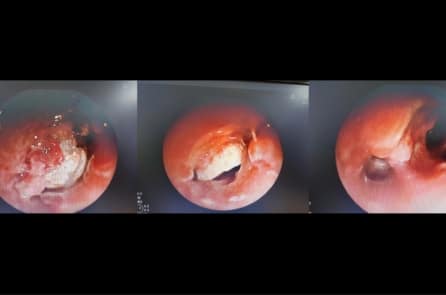

Hạt hạnh nhân mắc kẹt 7 ngày trong phế quản thiếu niên 15 tuổi

Khi bệnh viện xác định được dị vật, bệnh nhân đã bị biến chứng xẹp phân thùy đáy – lưng phổi trái kèm theo tràn khí trung thất. Nếu không được xử trí kịp thời,…